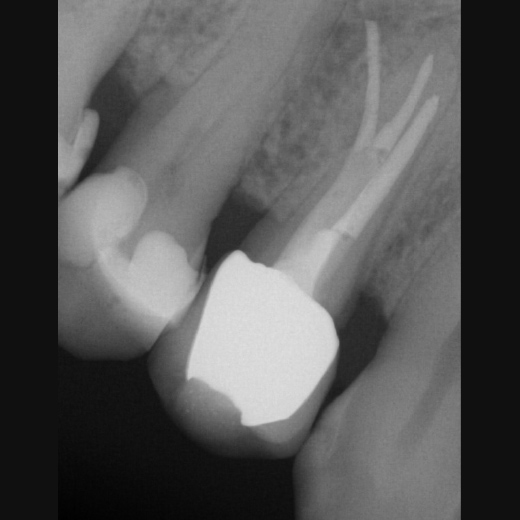

Fallbeispiel: Revision 46 (und 45) Recall 6 Monate

Bringt eine Wurzelkanalbehandlung nicht den gewünschten Erfolg, bedeutet dies nicht, dass ein Zahn nicht mehr zu erhalten ist. Mit einer Revisionsbehandlung können auch bereits wurzelkanalbehandelte Zähne langfristig erhalten werden!